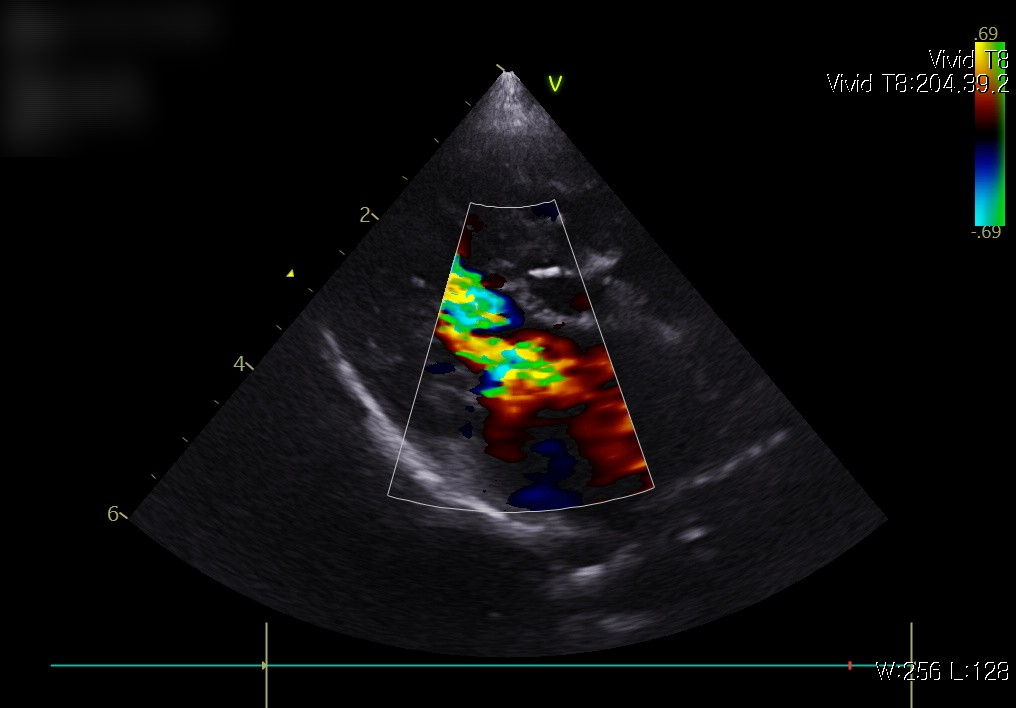

📌 심장 초음파

초음파 검사는 심장의 구조와 기능을 직접 확인할 수 있는 가장 중요한 검사입니다. 판막이 제대로 닫히는지, 심실 벽의 두께는 정상적인지, 혈액이 원활하게 흐르는지를 정밀하게 평가할 수 있습니다.

내원 즉시, 적극적인 산소처치와 안정화가 먼저 이루어졌습니다. 호흡곤란 환자는 응급 상황으로 진행될 수 있기 때문에, 빠른 산소 공급과 안정을 통해 위험을 줄이는 것이 최우선입니다. 이후 상태가 안정되자 심장 초음파와 흉부 방사선을 통한 정밀 진단이 진행되었습니다.

심장 초음파 사진: 판막 기능 이상과 혈류의 역류 소견 확인

검사 결과 심부전 소견이 확인되었고, 이에 따라 약물 관리를 통한 환축 안정화를 목표로 치료를 시작했습니다.